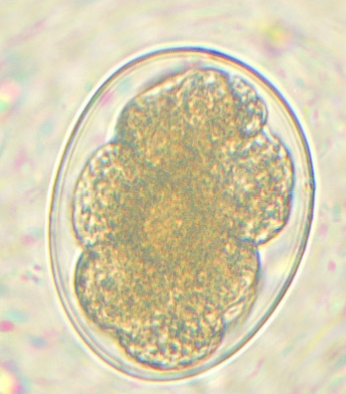

Cyclospora cayetanensis